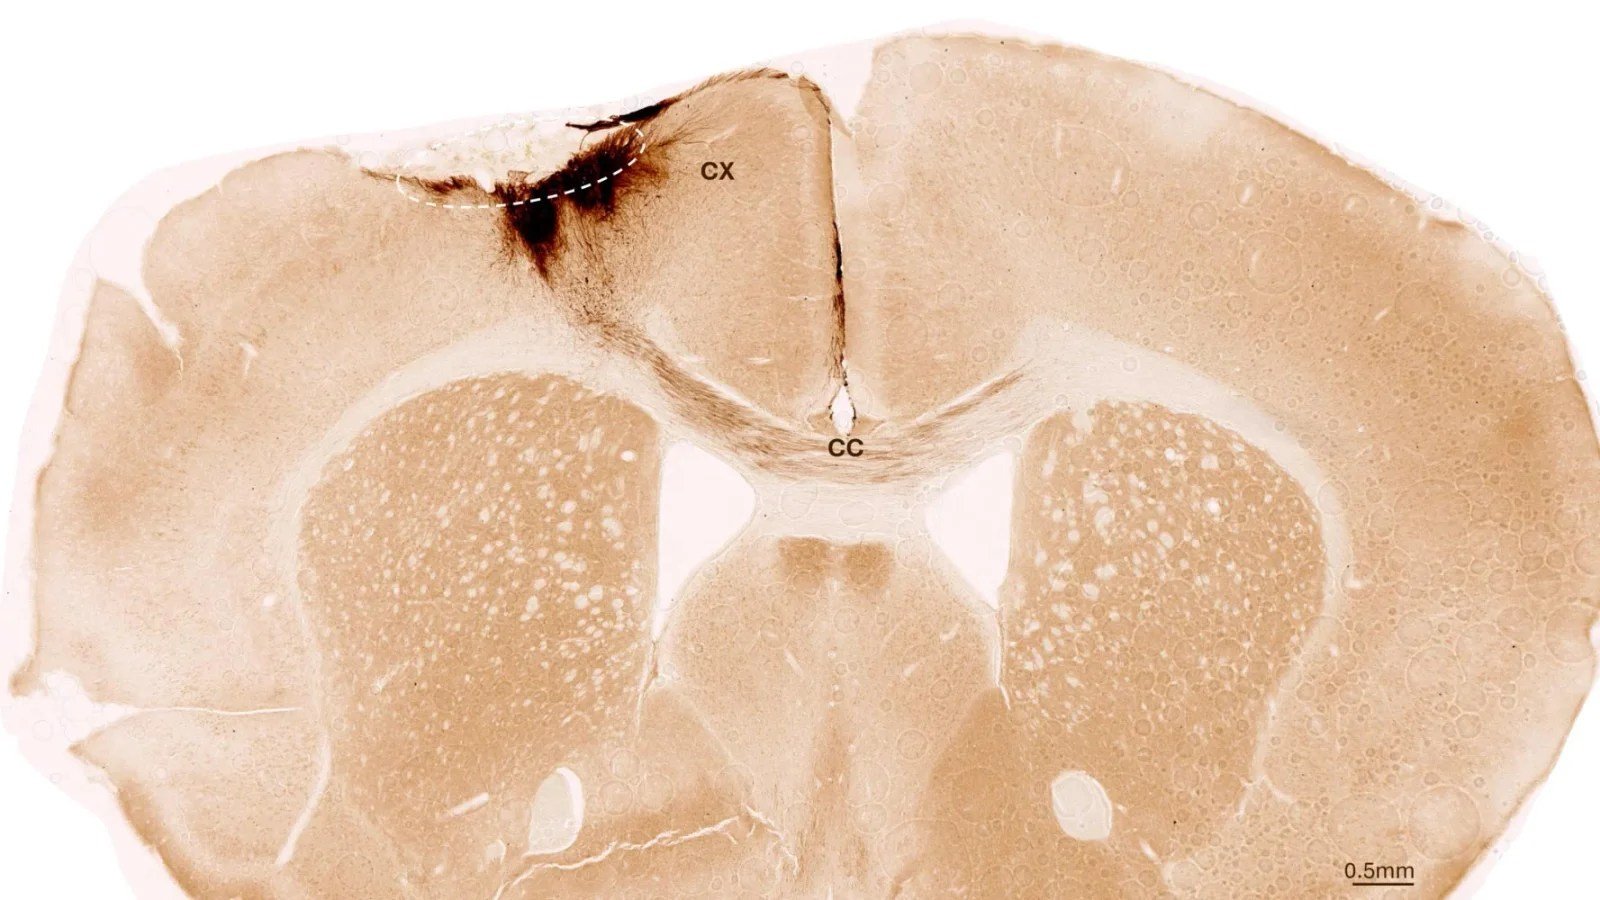

This image shows a coronal section through the mouse brain after stroke and neural stem cell transplantation. The dashed circle indicates the stroke area. The neurite projections of the transplanted human cells are stained in dark brown. Neurites extend locally into the cortex (CX) but also via the corpus callosum (CC) into the other brain hemisphere. Credit: University of Zurich